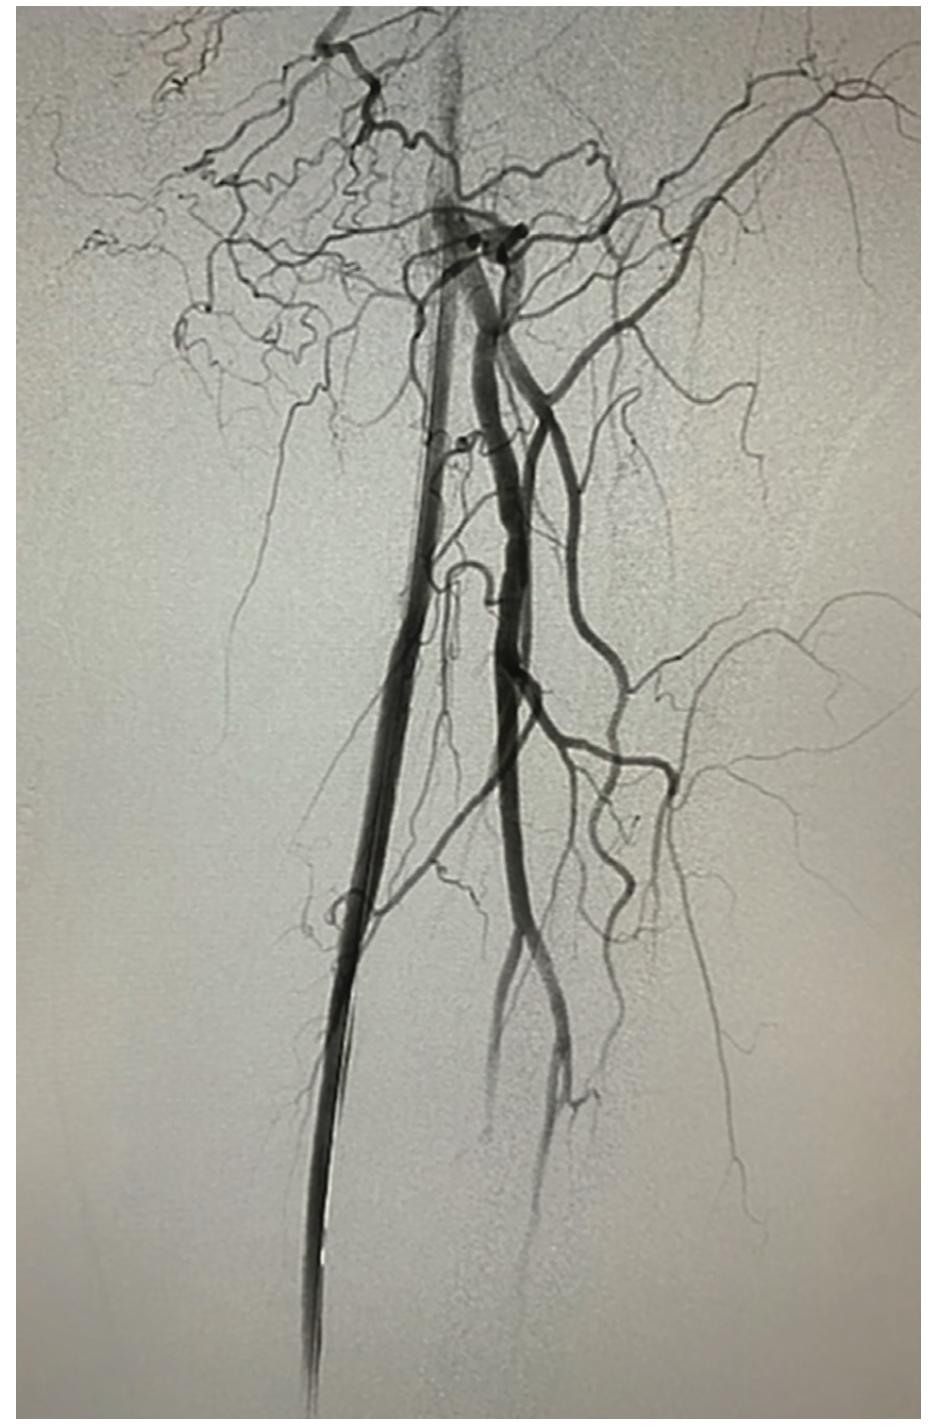

Following the diagnostic angiogram, we initially upsized to a 6 French 45 cm sheath (Cook Medical) and an .035-inch 260 cm Zip wire (Boston Scientific) did take the initial channel of the SFA. An .035-inch Rubicon microcatheter (Boston Scientific) was advanced and the wire was switched out to a Gladius .018-inch (Asahi Intecc). The knuckle was advanced distally, but did not re-enter at the reconstitution point. There was some diffuse disease distal to the reconstitution point and the goal was to not extend the dissection plane. Initial attempts were made to redirect with an .014-inch Halberd (Asahi Intecc) and penetrate the cap that way; however, it deflected off the distal cap. Pedal access was considered, but had an initial difficult access secondary to poor imaging and patient cooperation. After reviewing the films, it appeared there was path from a collateral off the profunda. The Halberd .014-inch wire was left in place as a marker wire. A Sion Black (Asahi Intecc) and a secondary microcatheter were advanced through the profunda and into the collateral. The wire was advanced through and came in right at the distal cap. Although we could not get enough purchase retrograde to advance a retrograde knuckle, the retrograde wire was able to manipulate the distal cap and caused some plaque modification (Figure 2). At that point, the antegrade Halberd wire was able to be redirected, entered the vessel at the reconstitution point, and wired distally. The .035-inch Rubicon microcatheter was advanced and switched out for a Sion Black. A 2.0 Auryon laser (AngioDynamics) with aspiration was used to performed laser atherectomy with <50 mL of aspirate (Figure 3). Total lesion length was approximately 220 mm. After about 2 minutes of treatment at 50 mmJ2, intravascular ultrasound (IVUS) (Boston Scientific) was performed, demonstrating a dissection distally at the cap. On pullback, there was diffuse plaque in the vessel but it was luminal (the proximal one-third of the vessel). Therefore, the plan was to treat the distal part of the lesion with a stent (to seal the dissection) and perform percutaneous transluminal angioplasty (after the laser) of the proximal vessel. After IVUS, we took a 5.0 mm x 200 mm Charger balloon (Boston Scientific), and inflated distally at 6 atmospheres and then to 10 atmospheres, and we came in proximal in the SFA. There was now reconstituted flow. The lesion distal to the reconstitution point was touched up with low-pressure balloon inflation, and then, based on the dissection plane, a 6 mm x 150 mm stent was placed. We did some post dilatation, and brisk flow to the SFA and no evidence of distal embolization were seen following angiography (Figure 4). The patient tolerated the procedure well. The wire was removed and repeat angiography demonstrated the same status: no dissection, perforation, or embolization.